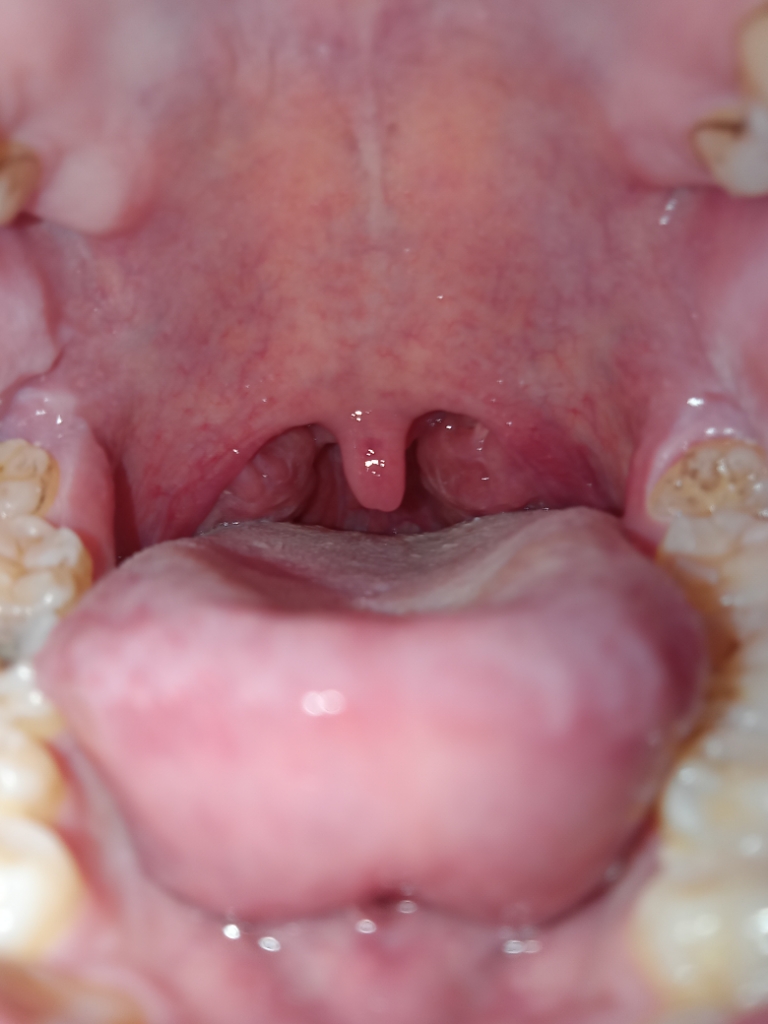

Em bị đau 1 bên amidan bên phải nuốt đồ ăn hay thè lưỡi ra thì rất đau lúc em soi gương thì thấy amidan bên phải sưng to hơn amidan bên trái thì e có sao ko ạ

Dạ đây ạ

Viêm amydal rõ rồi

Em dùng đơn thuốc trị amydal như kháng sinh, chống viêm, súc họng nước muối